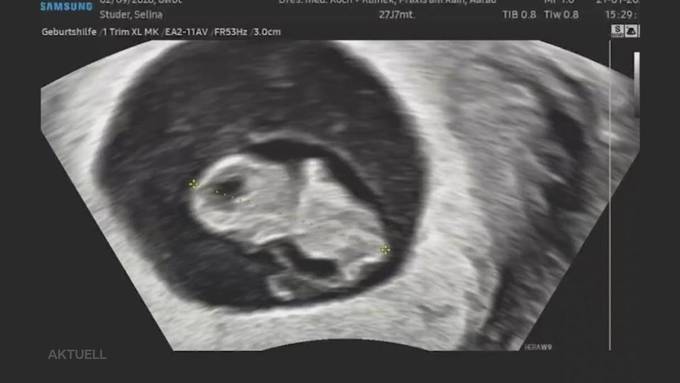

Während mehreren Jahren hat William W. immer wieder Kinder missbraucht. Das Gericht hat den heute 49-jährigen Mann mehrfach verurteilt und schlussendlich verwahrt. Für die Opfer ist das eine Erleichterung. Auch für Selina S. Heute blickt sie nach vorne. 2026 soll ihr Jahr werden, sie ist schwanger und erwartet ein Kind. Konnte Selina S. mit dem tragischen Fall definitiv abschliessen?